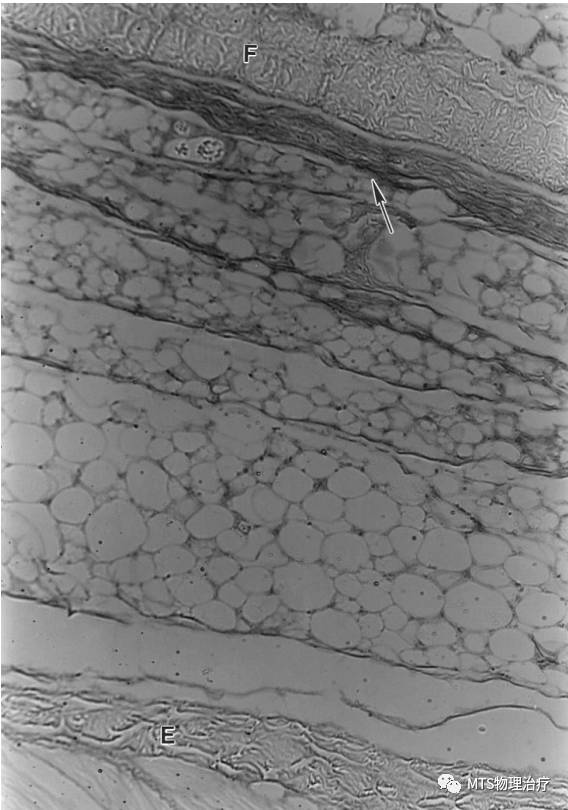

透明质酸在深筋膜深层或者肌表面存在,深筋膜在肌外膜和蜂窝组织间形成滑动界面。

在踝及腕部的支持带发现三层独特结构, 内层滑动层, 含透明质酸分泌细胞。

运动后透明质酸的潴留,当然在肌内膜中亦有, 这与透明质酸作为一种润滑剂,有促进肌纤维之间滑动的概念相一致。